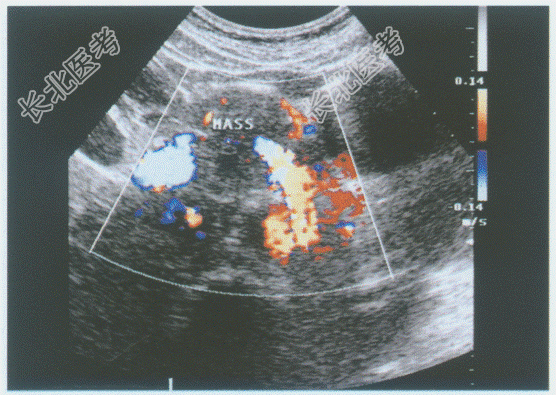

超声综合描述: 腹主动脉下腔静脉前方,胰头右侧可见3.6cm×3.4cm圆形低回声区, 边界清晰,包膜完整, 内回声尚均匀,CDFI: 内未明显血流信号,周边可见血管绕行。见下图及彩图。